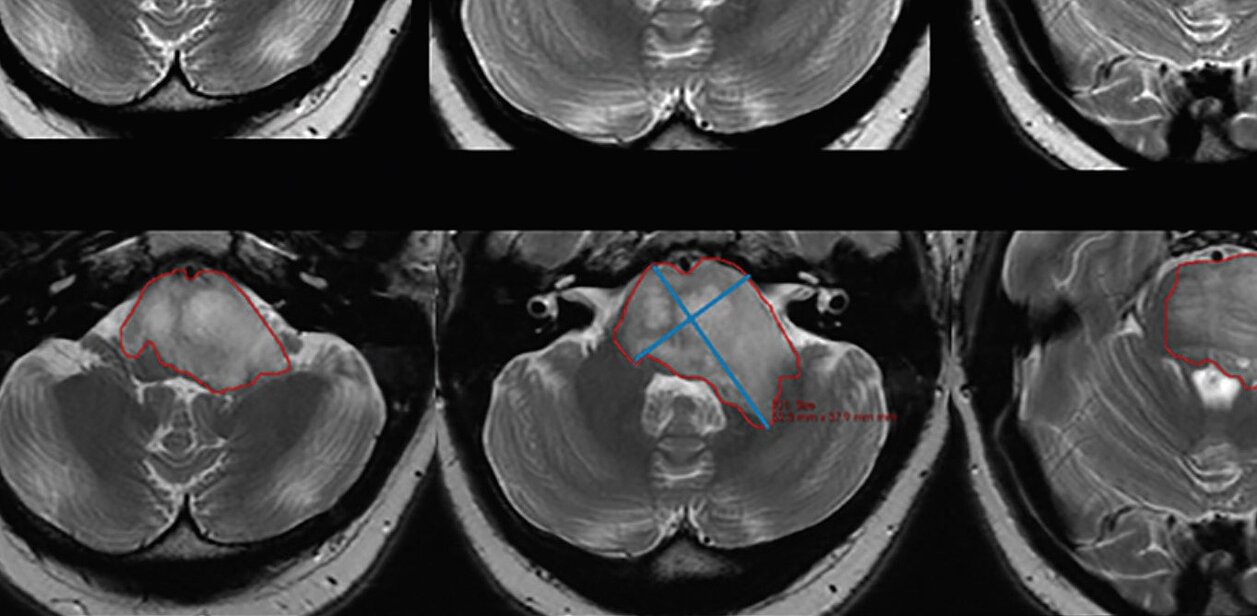

Im Rahmen einer Phase I/II-Studie für Ribociclib (Novartis, ClinicalTrials.gov Identifier: NCT02607124) wurden zehn Patienten prospektiv rekrutiert, die sich vor und nach der medikamentösen Behandlung einer MR-Bildgebung unterzogen. Die klinischen 2D-Kreuzproduktwerte wurden durch Multiplikation von manuell gemessenen linearen Längs- und Kurzachsen berechnet; zur automatischen Ableitung des maximalen Kreuzprodukts und des Tumorvolumens wurde mint Lesion™ verwendet.

Der Vergleich der drei Messstrategien zeigte die schwächste Korrelation der Veränderung der Tumorgröße zwischen manuellen 2D- und halbautomatischen 2D-Messungen (r = 0,36, P = .011). "Manuelle 2D-Kreuzrproduktmessungen können die Tumorgröße und den Krankheitsverlauf im Vergleich zu halbautomatischen 2D- und volumetrischen Messungen unterschätzen", stellten die Forscher fest. Es wird vermutet, dass diese Diskrepanz ihren Ursprung in der variablen Morphologie der DIPGs hat, aber auch in der Wahl der Messschicht und der -orientierung für die sich Radiologen oft ähnlich wie bei früheren Untersuchungen entscheiden. Dies wurde auch durch die Ergebnisse der Studie bestätigt mit "wichtigen Implikationen für den Einsatz von Segmentierungssoftware in der klinischen Praxis".